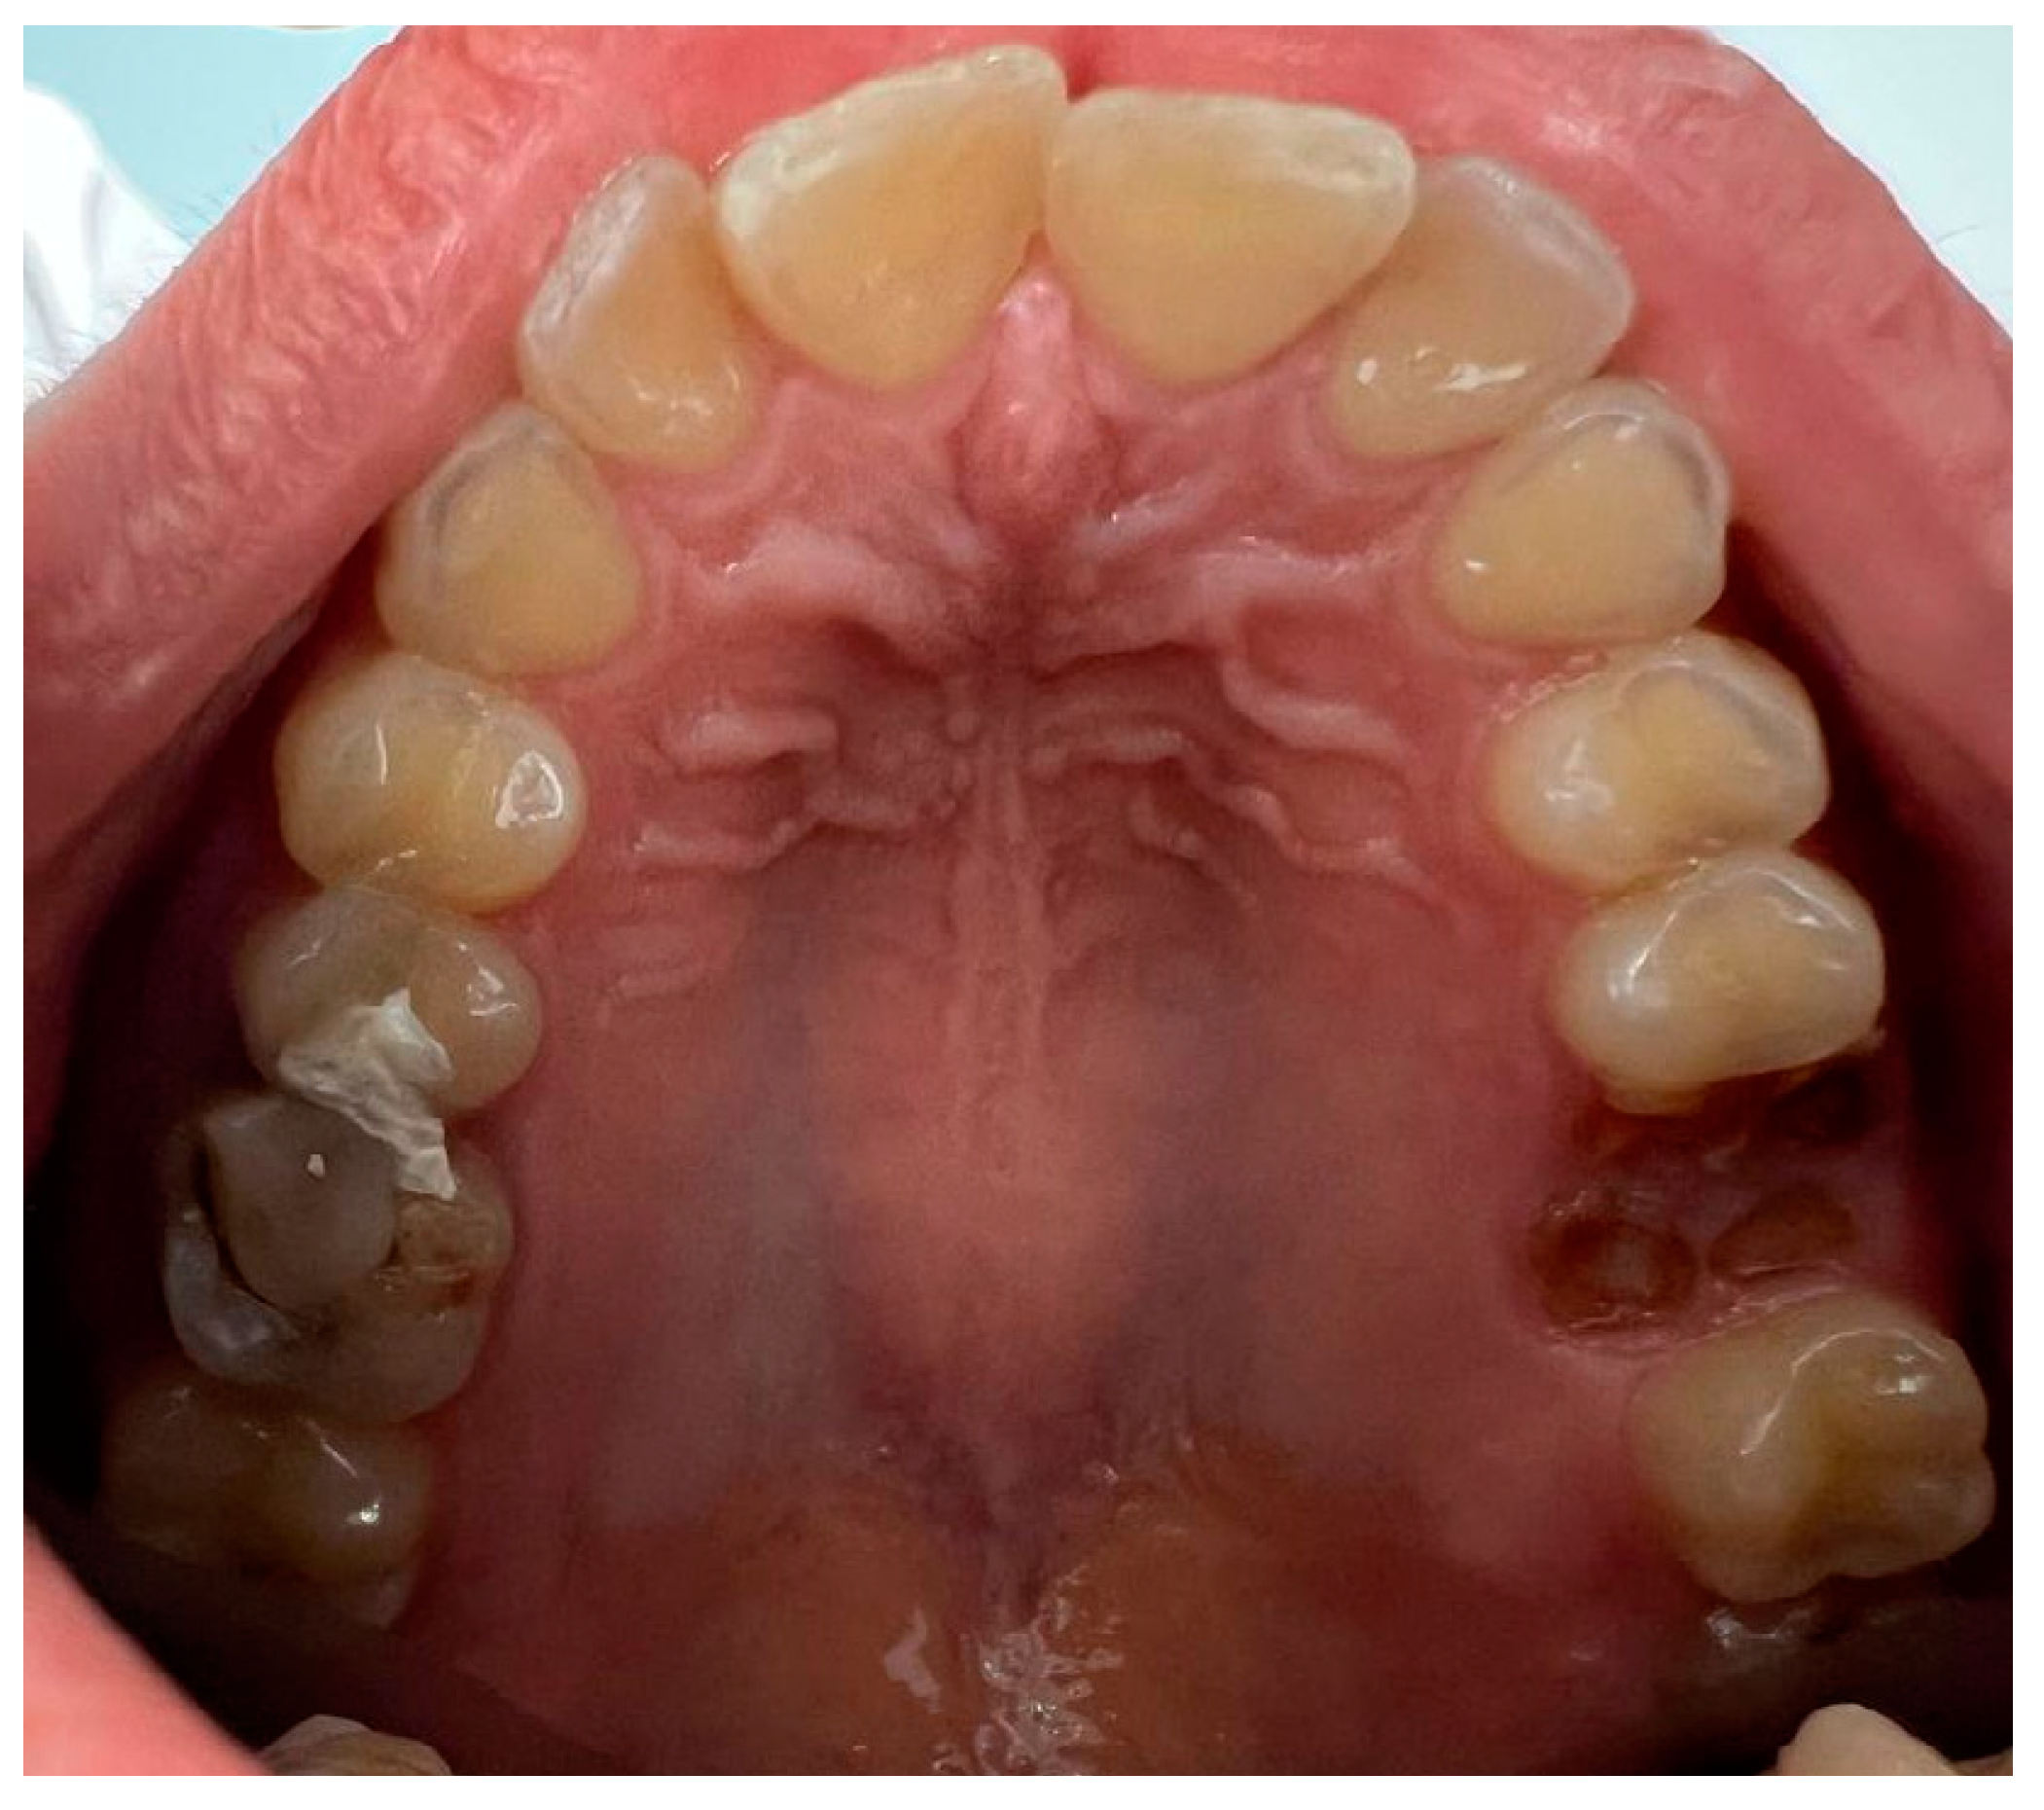

| Torus palatinus (TP) | 14 (11.5) |

| Torus palatinus | 11 (14.3) | 3 (6.7) | 14 (11.5) | 0.466 |

| Flat | 7 (63.6) | 3 (100.0) | 10 (71.4) | |

| Spindle-shaped | 2 (18.2) | 2 (14.3) | ||

| Nodular | ||||

| Lobular | 2 (18.2) | 2 (14.3) | ||